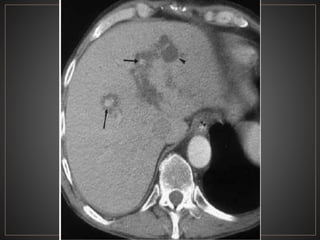

• 48.

CPRE: Dilataciones saculares de CBIH. TC: Simple:Áreas redondas, hipointensas en topografía de CBIH. Contraste: Signo del punteado central. RM: T2: Espacios quísticos hiperdensos